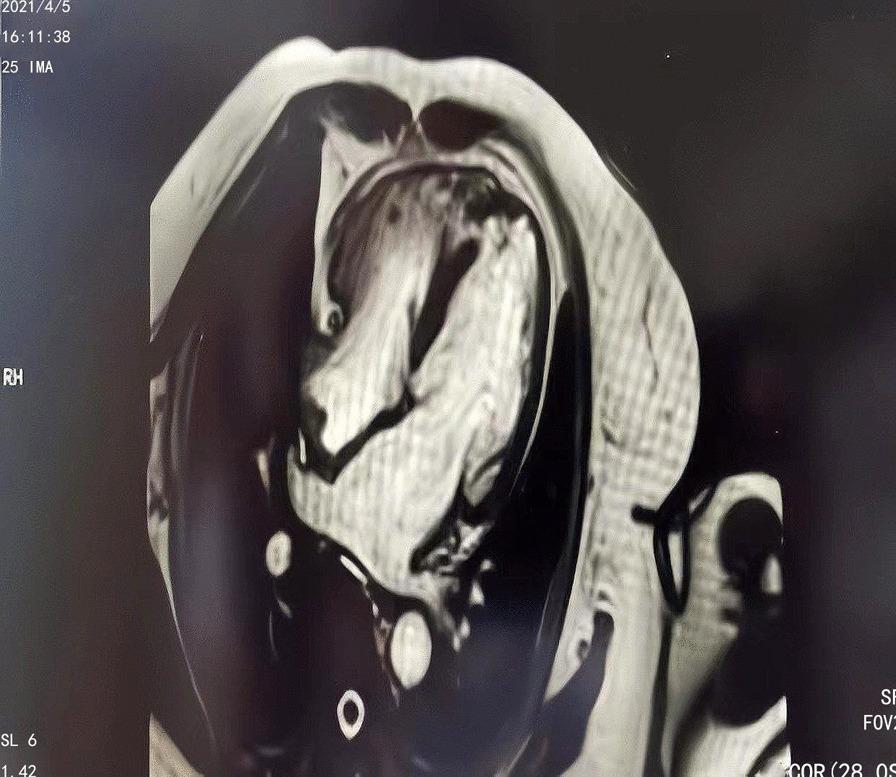

A 77-year-old female patient presented to the hospital with unrelieved chest tightness and shortness of breath. Three months ago, the patient's electrocardiogram revealed ischemic T wave inversion of the anterior wall, along with an increase in myocardial injury markers. There was no evidence of a ventricular septal defect on echocardiography. The patient was admitted to the respiratory department to treat lung lesions. The electrocardiogram demonstrated dynamic changes following admission, and the myocardial markers returned to normal, but the echocardiography revealed a ventricular septal defect. The initial diagnosis was ventricular septal perforation because of myocardial infarction with acute anterior ST-segment elevation. Coronary angiography revealed no abnormalities, but left ventricular angiography revealed an enlarged apex and VSD, with a right ventricular shunt bundle. Later, cardiac MRI revealed an apical ventricular septal defect. Further inquiry of the patient's medical history revealed that her husband died unexpectedly three months ago, and her daughter was seriously injured in a car accident, causing the patient severe emotional distress. Takotsubo syndrome was then determined in conjunction with the patient's medical history, symptoms, signs, and pertinent examinations. Without using a catheter or a surgical procedure, we managed the patient's medical condition. Two weeks later, the patient was discharged with symptoms improved.

一名 77 岁女性患者因持续的胸闷和呼吸急促到医院就诊。三个月前,患者的心电图显示前壁缺血性 T 波倒置,同时心肌损伤标志物升高。超声心动图未见室间隔缺损。患者因肺部病变入住呼吸科。入院后心电图显示动态变化,心肌标志物恢复正常,但超声心动图显示室间隔缺损。最初的诊断是由于急性前壁 ST 段抬高型心肌梗死导致的室间隔穿孔。冠状动脉造影未见异常,但左心室造影显示心尖部扩大和 VSD,并伴有右心室束分流。后来,心脏 MRI 显示心尖部室间隔缺损。进一步询问患者病史发现,她的丈夫三个月前意外去世,女儿在车祸中受重伤,这让患者情绪极度痛苦。结合患者的病史、症状、体征和相关检查,诊断为 Takotsubo 综合征。我们没有使用导管或手术来治疗患者的病情。两周后,患者症状改善出院。